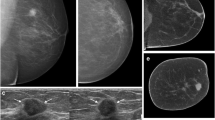

Diagnostic test accuracy results by each imaging modality are summarised in Table 3. Figures 2 and 3 aid in visual interpretation of the imaging modality accuracy and reader performance. Case reports demonstrating all imaging modalities in type c and type d density breasts are shown in Figs. 4 and 5.

A 51-year-old woman without clinical symptoms presented for routine mammography. a Diagnostic mammography in cranio-caudal view detected only a few microcalcifications, which were detected and judged as benign (arrows). The MG showed an ACR density type c of the breast. b In US, an associated hypoechoic mass with indistinct margins and with dorsal shadowing was seen (arrowheads). c With MG and corresponding NC-CBBCT the mass was not detected by both readers; only the microcalcifications were identified by one reader as malignant (arrows). d Corresponding CE-CBBCT and MRI showed an intensive enhancement of a mass (e) and an associated non-mass enhancing area (f), detected by both readers and was proved by surgery to be an invasive ductal carcinoma [(IDC) 24 mm] with ductal carcinoma in situ (DCIS), intermediate grade. The extent of this IDC with DCIS could only be correctly assessed by the contrast-based methods